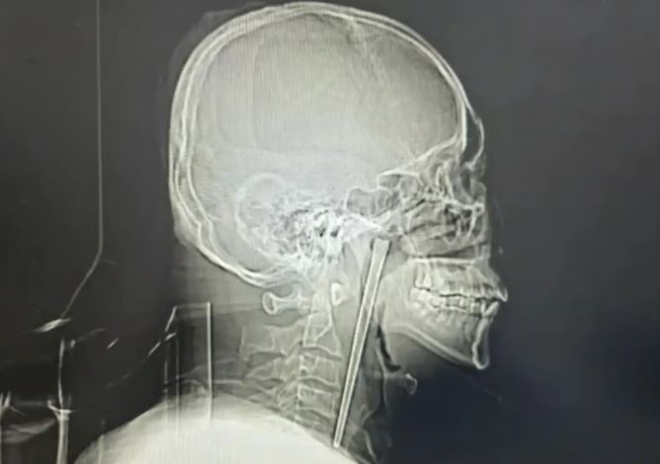

술 마시다 12cm 젓가락 ‘꿀꺽’…수술 무서워 8년 버틴 中 남성, 결말은